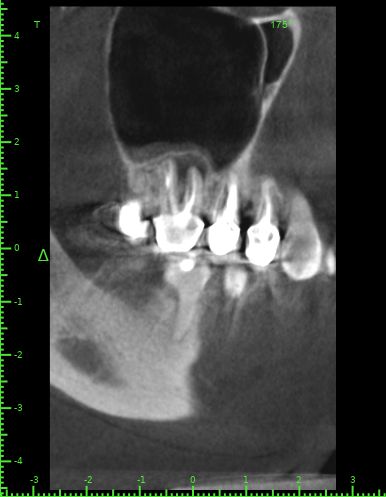

Katya88 Опубликовано 28 июля, 2021 Поделиться Опубликовано 28 июля, 2021 Мой стоматолог терапевт советует удалить, так как там кисты, а ортопед советует найти того, кто займется лечением. КТ прилагаю https://drive.google.com/file/d/1Z-neEH63BszTXxa8bAOG1tgsrIrsqrVK/view?usp=drive_web Ссылка на комментарий

Женька Опубликовано 28 июля, 2021 Поделиться Опубликовано 28 июля, 2021 2.6 2.7 3.7 На 3.5 и 1.5 стоит обратить внимание 1.5 1 Ссылка на комментарий

Женька Опубликовано 28 июля, 2021 Поделиться Опубликовано 28 июля, 2021 54 минуты назад, Katya88 сказал: 1.5 менять коронку как минимум снять существующую конструкцию и посмотреть клинически на зуб(ы). 1.5 на КТ выглядит удручающе. По остальным, я бы поддержал ортопеда и попытался зубы сохранить. Пусть коллеги меня поправят. 1 1 Ссылка на комментарий